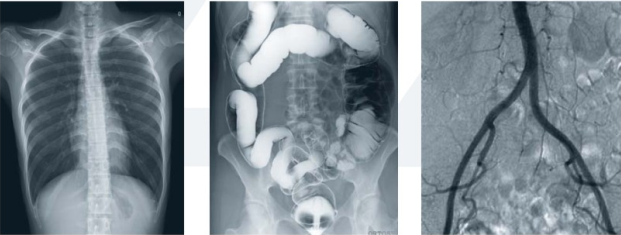

普利德品牌的动态DR具备动态影像视频实时回放功能,探测器采集大幅面,进行穿透、胃肠、造影检查更加方便、准确,明显提高检查效率及诊断质量。操作简单快捷,一键到位。充分体现人性化设计理念,可根据检查部位的不同wsgtexr调整采像速度,实时采集高品质影像;人性化设计的检查床,无需移动病人即可完成各项检查。具有自动亮度跟踪功能,在方便操作的同时,通过自动优化曝光剂量获得优异的影像图片,有效降低X射线辐射剂量,保护医患身体健康。

拥有先进的数字化图像处理技术,保证优异的动、静态图像质量。动态CCD探测器技术,可进行高像素动、静态图像转换,采集的图像具有信息量大、对比度高和动态范围宽的特点,成像质量明显优于普通胃肠机,为医生的临床诊断提供更优异的影像数据,大幅提高医院的工作效率。想了解产品具体信息,欢迎留言或致电400-6656-888